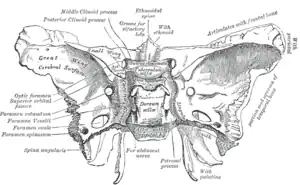

The tumor is difficult to detect by CT due to decreased sensitivity of the scan at the level of the sella turcica. MRI is the primary imaging modality for detection, with the lesion being of similar signal intensity to gray matter and non-enhancing with contrast. Lack of enhancement is an important imaging characteristic to help distinguish the tumor from similar masses that can occur in this region. These include germ cell tumors, granulomas of Langerhans cell histiocytosis and hypothalamic astrocytomas, as these lesions usually demonstrate at least partial uptake of contrast.[1]

Surgery is offered if there is failure of medical therapy or rapid growth of lesion, with specific options including stereotactic thermocoagulation, gamma knife radiosurgery, and physical resection by transsphenoidal microsurgery. Surgical response is typically better when the seizure focus has been found by EEG to originate in or near the mass. The specific location of the lesion relative to the pituitary and infundibulum and the amount of hormonal disturbance at presentation can help predict risk of hypopituitarism following surgery.[8]